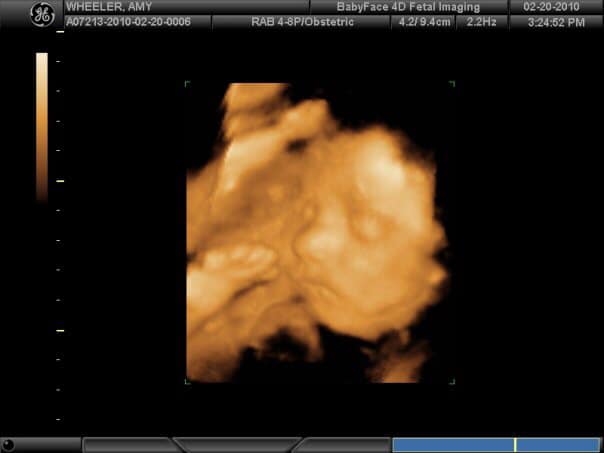

In the business of pregnancy and birth, we know how valuable doctors can be to you and your family. We strive to help make your pregnancy experience memorable by providing the perfect way to capture your baby’s heartbeat, but the truth is that we wouldn’t have a business without the doctor that help ensure you and your baby are healthy.

As a woman learns she is pregnant, her body may have no outward signs. This does not mean that nothing is changing. There is so much happening within her that may not be visible to the naked eye.